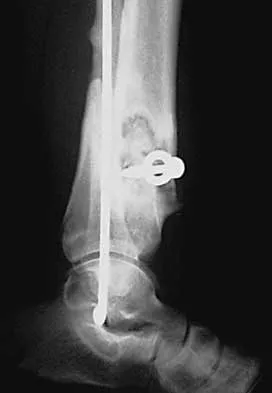

Figures 12a through 12e show the radiograph, MRI scans, and biopsy specimens of a 17-year-old boy. What is the most likely diagnosis?

The images show an epiphyseal lesion. The MRI scan shows extensive bone edema surrounding the lesion, consistent with chondroblastoma. Histology shows polygonal chondroblasts in a cobblestone-like pattern and areas of calcification consistent with chondroblastoma. Although some giant cells are seen, the age of the patient and the polygonal chondroblasts differentiate this lesion from giant cell tumor. Clear cell chondrosarcoma is an epiphyseal lesion that occurs in an older population, and the cells have clear cytoplasm. This lesion is not producing bone on imaging or histologic specimen, eliminating osteosarcoma. Tuberculous septic arthritis can be an epiphyseal lesion, but granulomas would be seen on histology. Menendez LR (ed): Orthopaedic Knowledge Update: Musculoskeletal Tumors. Rosemont, IL, American Academy of Orthopaedic Surgeons, 2002, pp 103-111.